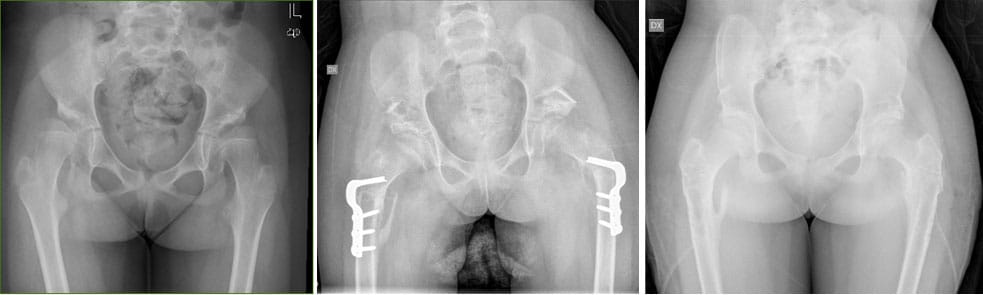

Pelvic and Proximal Femoral Osteotomies Pre – post surgery and follow up (2 years later)

- Osteotomy of the proximal femur to center the femur head within the acetabulum, which sometimes includes reconstruction of the acetabulum itself.